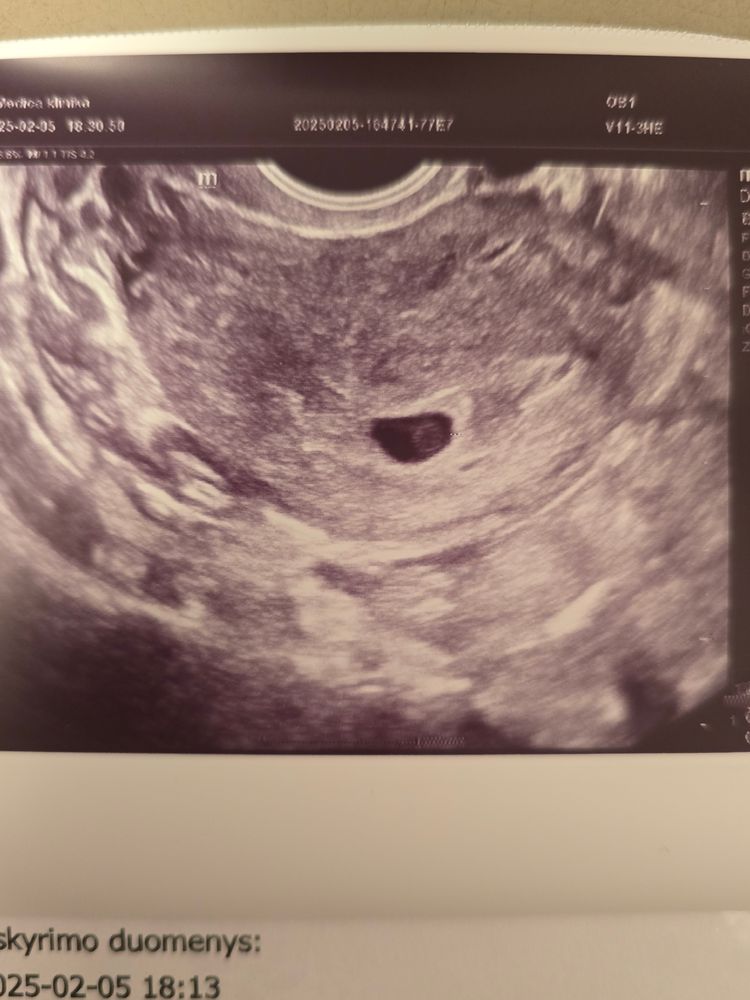

Наши будни, наши неделькиВчера было 5+1. Если учесть, что это 4 Б, вторая и третья были ЗБ на 5+4 и 6+3 соответственно, то сейчас самый стресс. Вчера соотвотствие 4+6, Г сказала, что всё соответствует, видно что-то похожее на эмбрион, показала, но не измеряла. ЖМ есть. Контроль в 6+3.

Фоточка красивая. Держись, крошечка ❤️